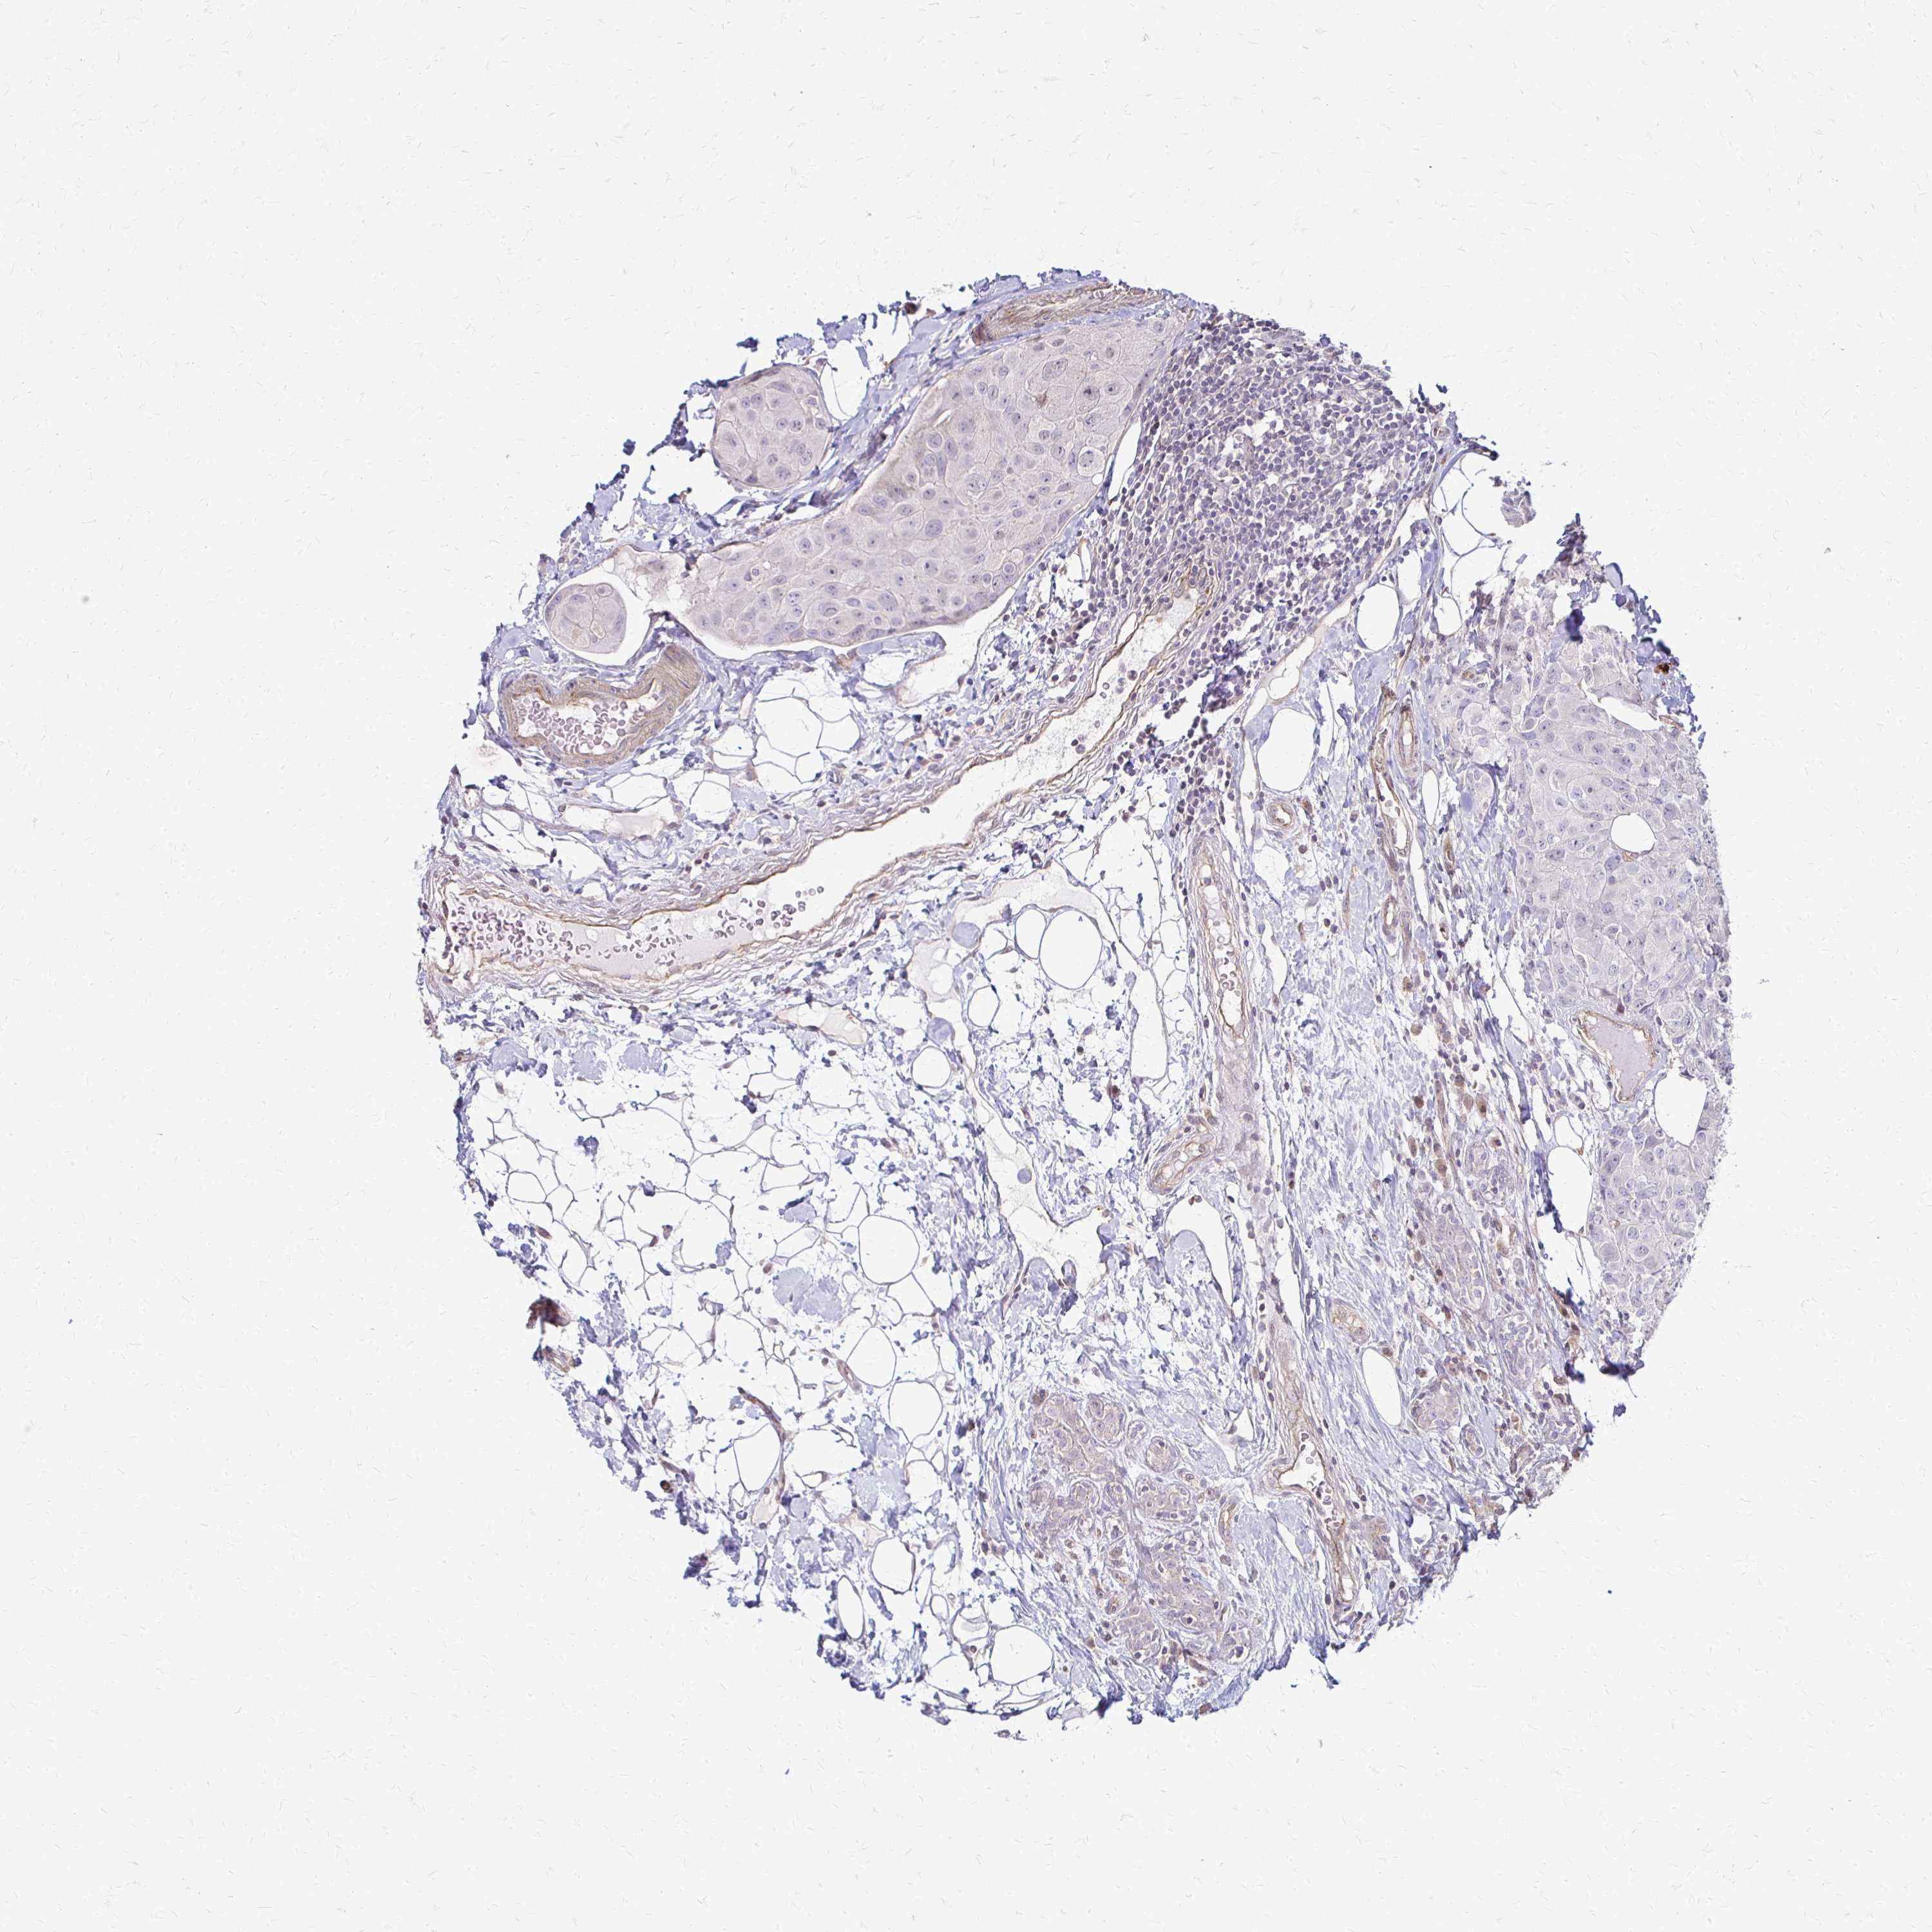

BRCA TCGA BRCA VALIDATION PROTEIN EXPRESSION

ANTIBODIES

AND

VALIDATION